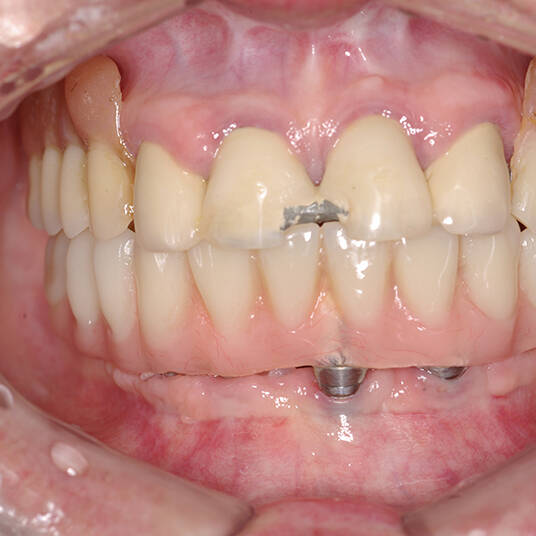

A Carga Imediata é uma técnica odontológica avançada que permite a colocação de uma prótese dentária fixa logo após a cirurgia de instalação dos implantes ou em poucos dias. Isso elimina a espera tradicional de meses para a integração completa do implante ao osso, oferecendo uma solução rápida e segura para restaurar dentes perdidos.

- Fixação da Prótese: Em até 72 horas após a cirurgia, a prótese provisória é instalada, permitindo que o paciente recupere a funcionalidade e a estética imediatamente.